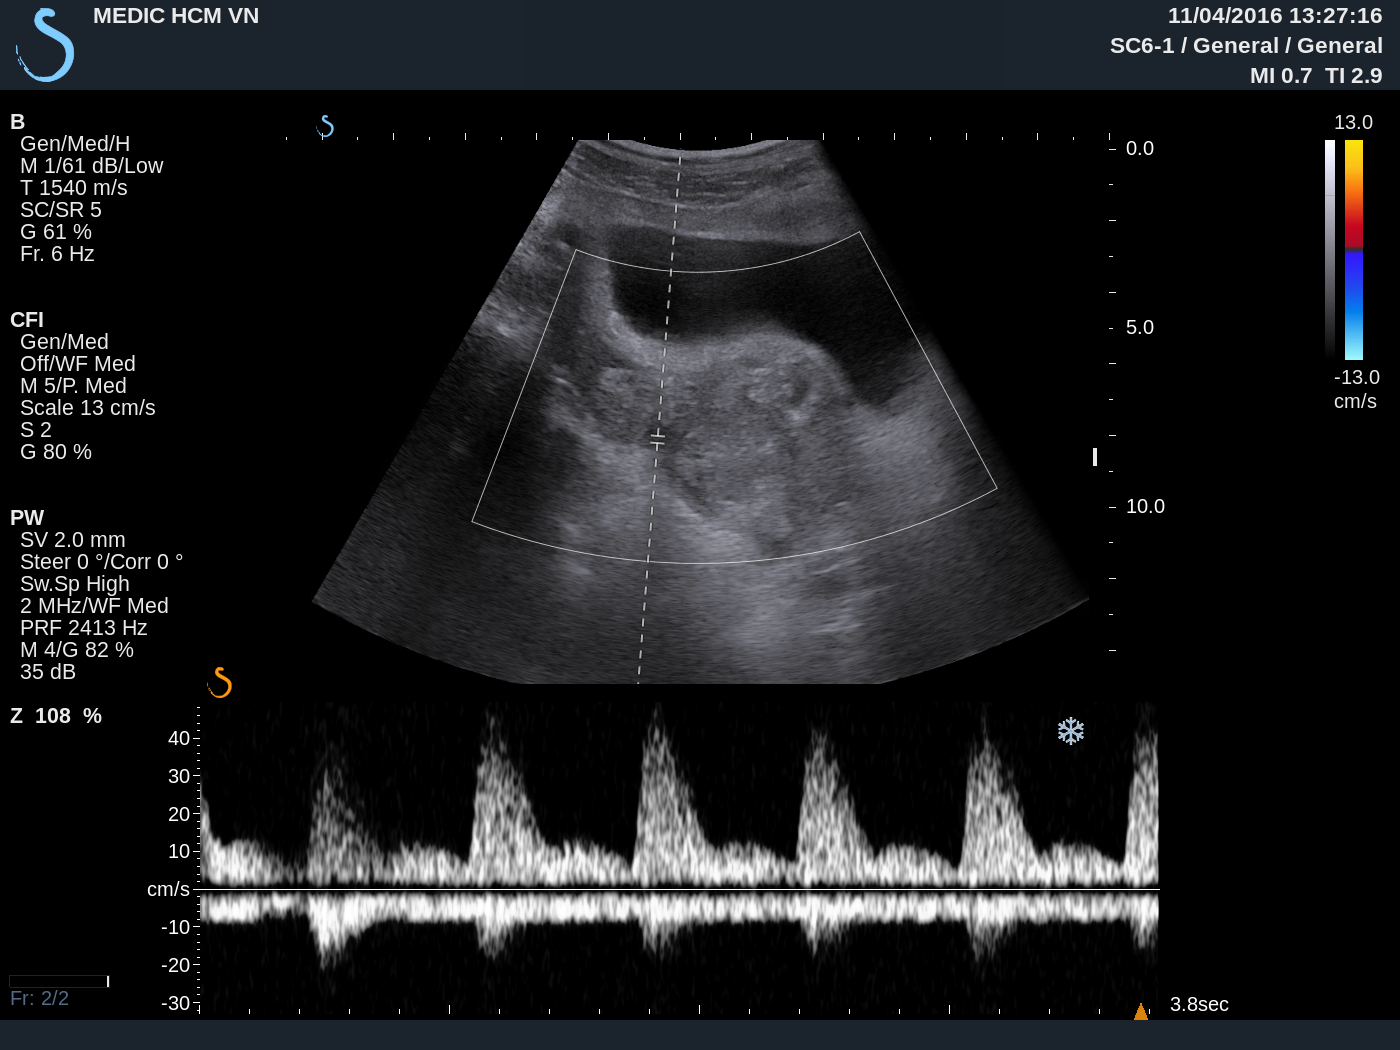

Ultrasound again detected one hypervascular mass at the neck of uterus ( see 3 USimages).

MRI uterusof this mass suspected gestation at neck uterus in the scar of cesarian section before.